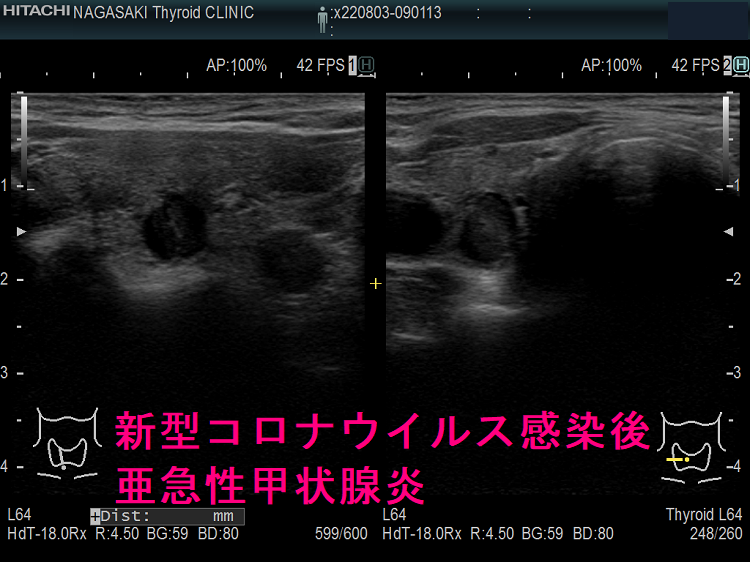

以下は、長崎甲状腺クリニック(大阪)の自験例です。

長崎甲状腺クリニック(大阪)の自験例

急性期

1.5か月後

5か月後